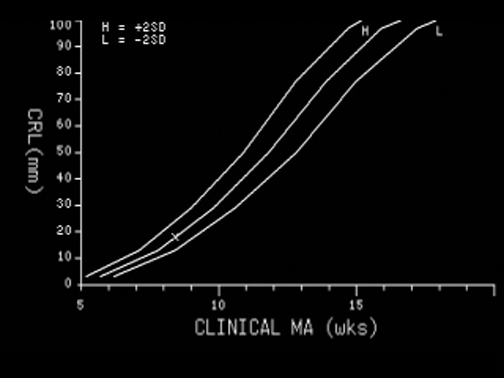

Measurement Graph |

Crown Rump Length (CRL) |